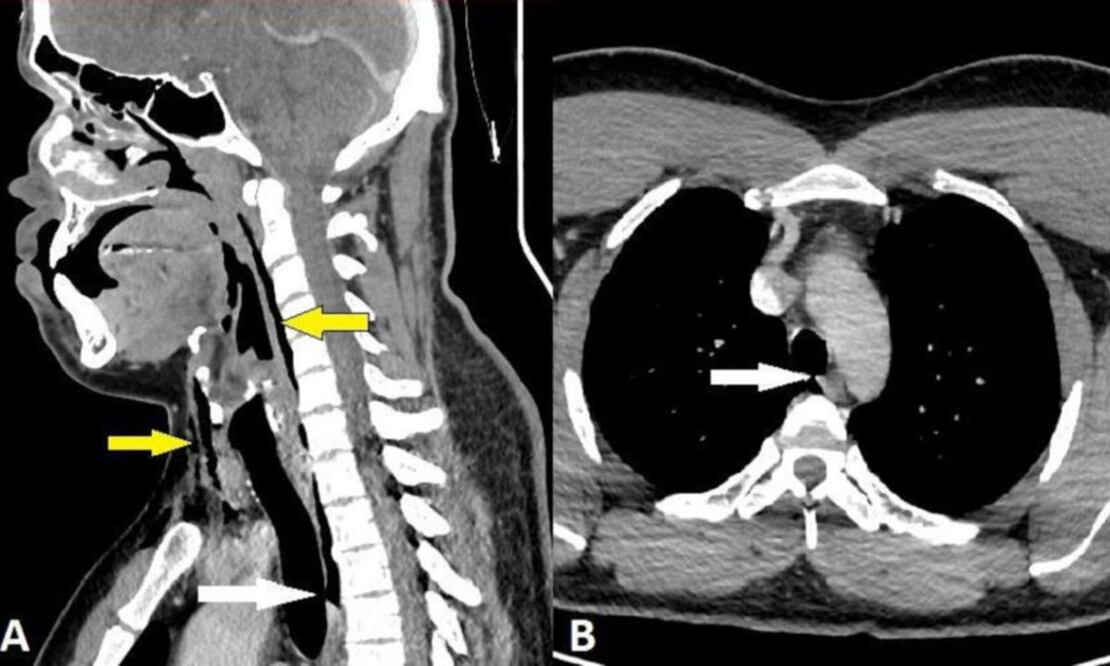

Le practicaron una radiografía que arrojó un enfisema quirúrgico, es decir, había aire en la capa más profunda de la piel, el tejido subcutáneo. Una tomografía computarizada de cuello y tórax añadió mayor sorpresa para los médicos, pues encontraron un desgarro traqueal a nivel de su tercera y cuarta vértebra torácica.

De acuerdo con lo explicado por Misirovs y su equipo, a la quinta semana lo sometieron a una nueva tomografía computarizada que les permitió concluir que se había recuperado.